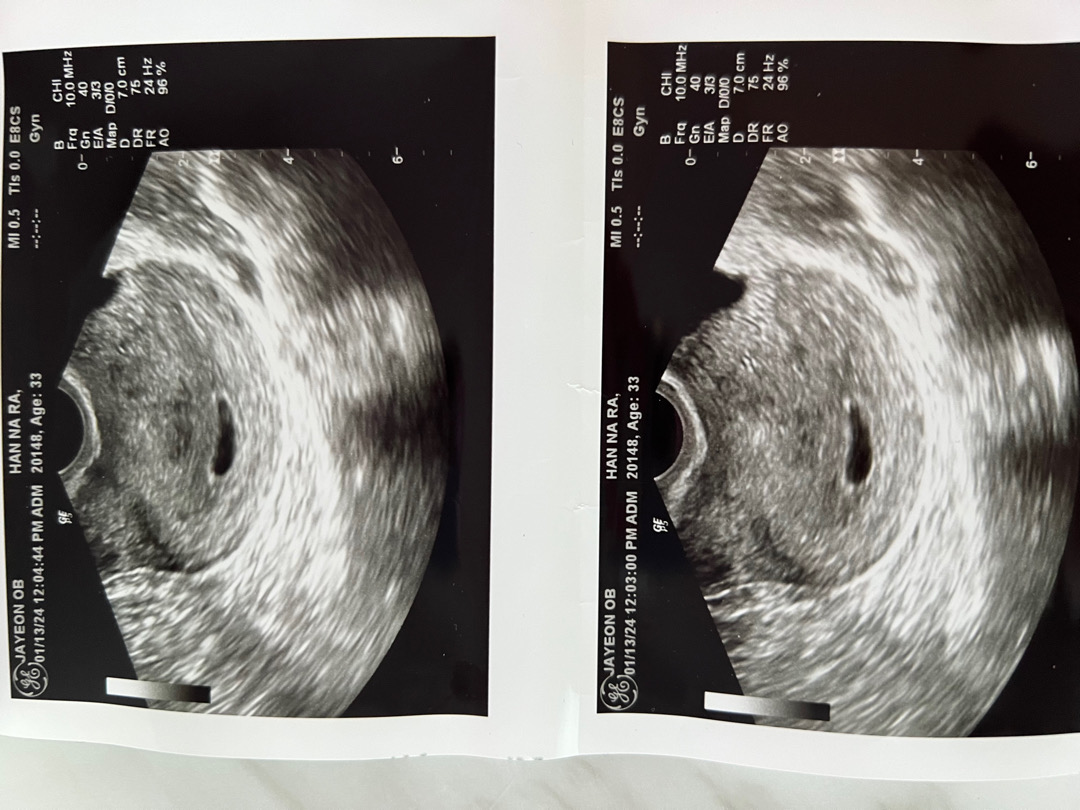

난황이 없대요.....

네이버주수 5주 6일이고 월요일에 초음파로 처음 아기집 확인했어요 2주뒤에 와서 심장소리 들으라했는데, 어제 열이나서 아기가 잘 있는지 보려고 방금 집앞에 산부인과갔다왔거든요..? 근데 난황이 없어요... 보통 이정도 크기면 난황이 보인다고 하는데 난황이없대요.. ㅠㅠㅠㅠㅠ 예상주수는 5주~5주 중반됐다고 하는데.. 이거 예후가 안 좋은 걸까요..?

저는 네이버주수 6주6일인데 오늘 난황이없다네요 ㅠㅠ 애기집크기도 작고 0.78정도..

초음파 화질 나빠서 그럴 수도 있어요 저는 병원 한 곳에선 엄청 선명하게 잘 봤는데 다른 곳에선 거의 안 보이다 시피 하더라구요 초음파 화질 좋은 병원에서 다시 한 범 보셔요